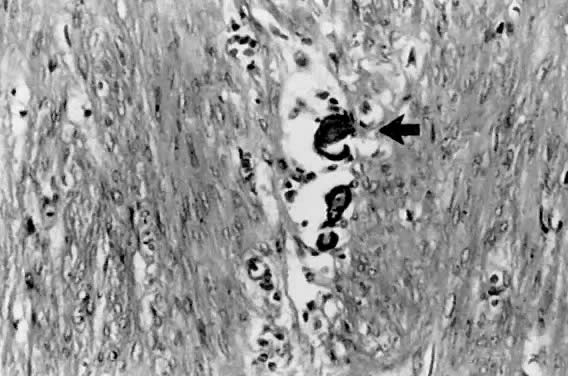

Fig. 12. Although more commonly seen in serous carcinoma, psammoma bodies ( arrow) may also be found in the villoglandular variant of endometrial carcinoma.

Serous carcinoma is a relatively uncommon type of endometrial carcinoma, accounting for about 5% to 10% of cases. This is an especially aggressive variant, with patients often presenting with stage II or III disease, deep myometrial invasion (40% to 50%), and frequent vascular invasion.21 The mean patient age is 70 years,45 somewhat older than for patients with endometrioid carcinoma. It occurs disproportionately in African-American women. Whereas about 53% of patients with endometrioid carcinoma have a history of exogenous estrogen use, only 21% of patients with serous carcinoma have such an association.21 Nulliparity is not a common epidemiologic factor in serous carcinoma. These tumors have a predilection for peritoneal spread, similar to primary ovarian serous adenocarcinoma.24 A papillary configuration is frequently present histologically (Fig. 10), but these lesions may grow in a solid or acinar pattern. For this reason, this variant should be referred to as serous carcinoma rather than papillary serous carcinoma. Papillae, when present, have fibrovascular cores that are lined by pleomorphic, hyperchromatic nuclei with eosinophilic macronucleoli (nuclear grade 3). Not infrequently, large, bizarre nuclei, often multinucleated, are observed. Cellular stratification and tufting or budding are frequently found (Fig. 11). The surface of the papillae are irregular and jagged, unlike the smooth surface of the villoglandular variant of endometrioid carcinoma. The solid or acinar patterns show cellular features as described above. Psammoma bodies (Fig. 12) are seen in about a third of cases. Due to the usually high nuclear grade, advanced stage of disease, deep myometrial invasion, and vascular space invasion, patients tend to have a poor prognosis, with a 25% to 35% 5-year survival rate45,46,47 and a 14% 10-year survival rate.47 Lung and liver are the most common sites of metastasis48 in advanced-stage serous carcinoma of the endometrium.